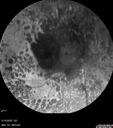

87 year old female. Severe macular bleed 15 years ago OD. Now with disciform scar. Left eye has progressing geographic atrophy. VA OD: HM, OS: 5/200. IOP normal OU